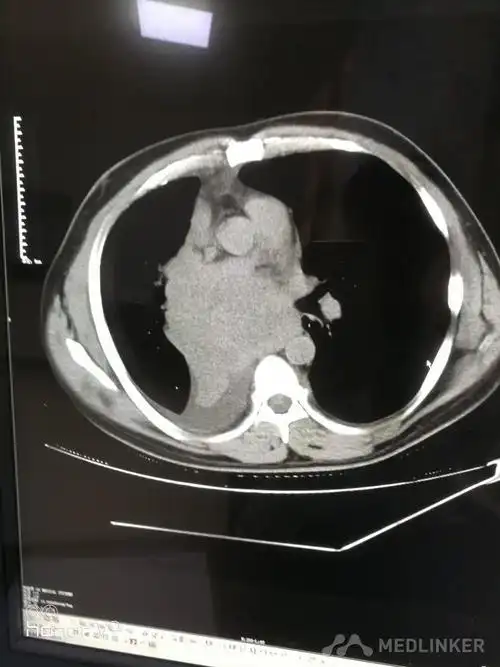

中央型肺癌的ct表现

中央型肺癌一例!

ct诊断中央型肺癌伴心脏转移一例

中央型肺癌一例直接征象和间接征象都有哪些